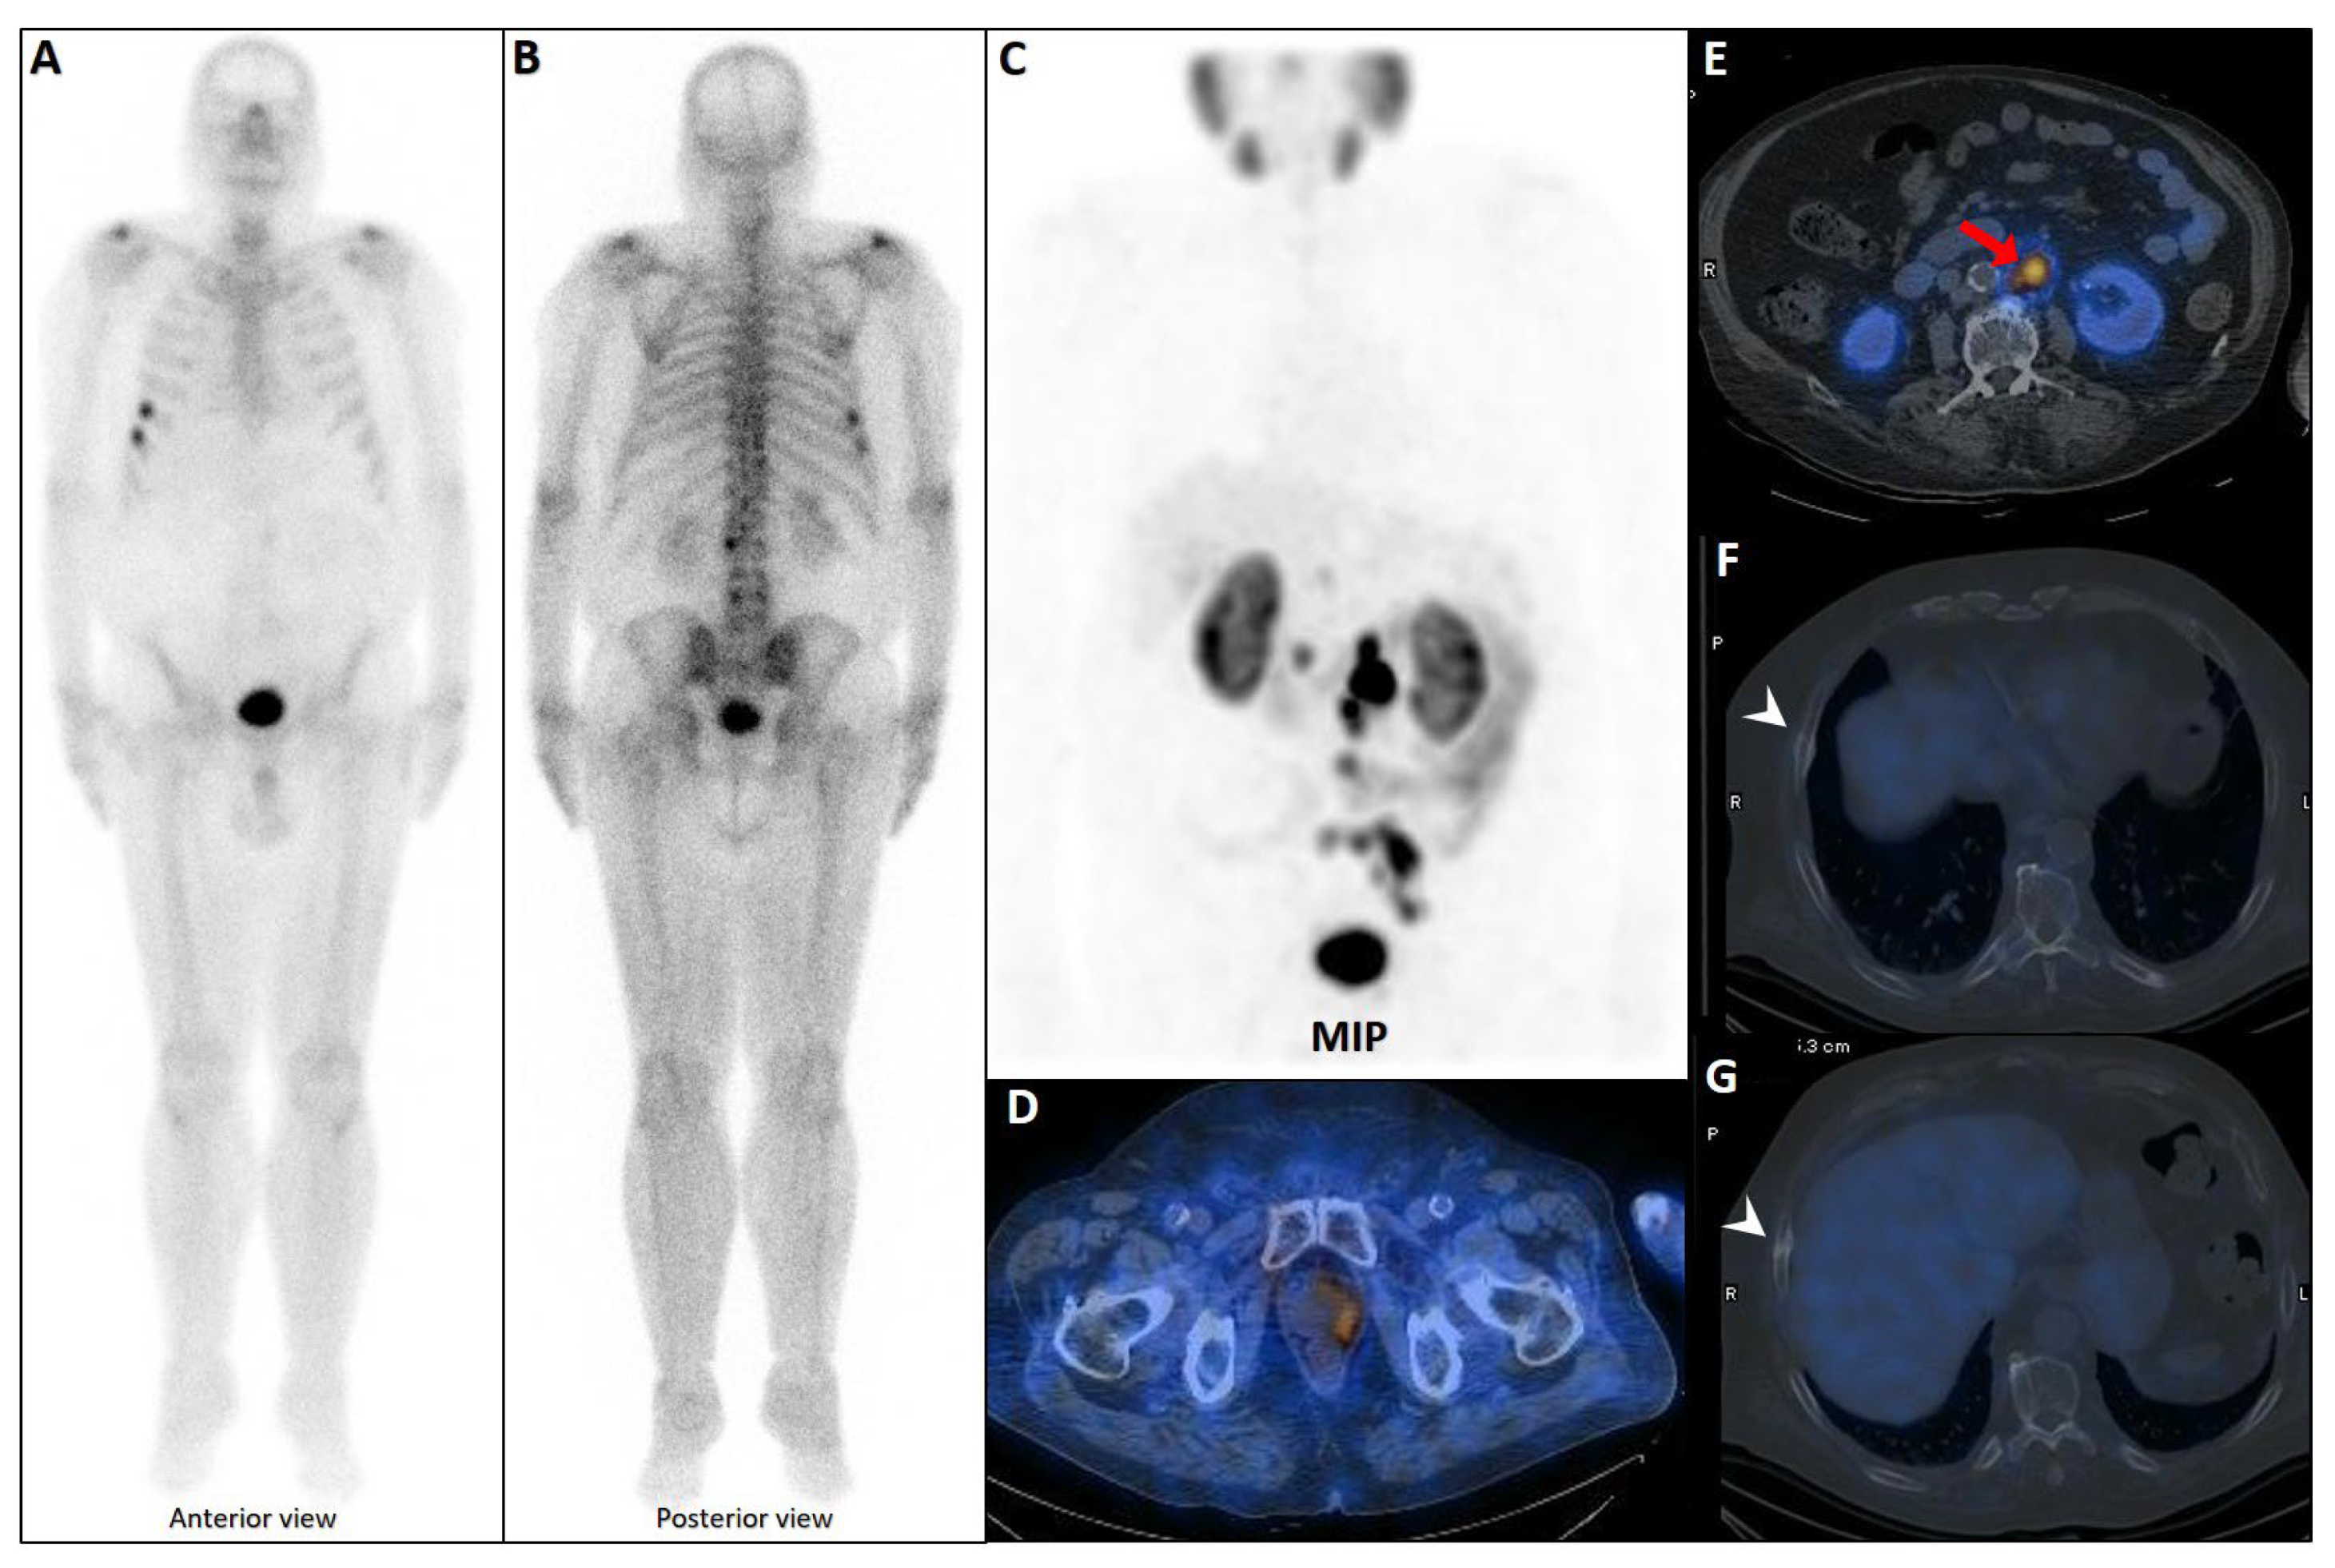

- Chiu, L.W.; Lawhn-Heath, C.; Behr, S.C.; Juarez, R.; Perez, P.M.; Lobach, I.; Bucknor, M.D.; Hope, T.A.; Flavell, R.R. Factors predicting metastatic disease in 68Ga-PSMA-11 PET–positive osseous lesions in prostate cancer. J. Nucl. Med. 2020, 61, 1779–1785. [Google Scholar] [CrossRef]

- Shah, N.; Sedeh, A.E.; Deffler, C.; Ng, T.S.C.; Mercaldo, N.; Gao, X.; Mahmood, U.; Heidari, P.; Esfahani, S.A. The role of PSMA PET/CT in distinguishing malignant from benign solitary bone lesions in prostate cancer patients. Clin. Imaging 2025, 125, 110570. [Google Scholar] [CrossRef] [PubMed]

- Luo, L.; Wang, Z.; Wang, X.; Gao, J.; Zheng, A.; Duan, X. Fluorine-18 prostate-specific membrane antigen-1007-avid indeterminate bone lesions in prostate cancer: Clinical and PET/CT features to predict outcomes and prognosis. Clin. Radiol. 2024, 79, 346–353. [Google Scholar] [CrossRef] [PubMed]

- Benecke, J.A.; Calderón, E.; Reischl, G.; Brendlin, A.; Tsaur, I.; la Fougère, C.; Vogel, J. Focal Unspecific Bone Uptake on [18F]PSMA-1007 PET: Evaluation Analog PROMISE Criteria and Validation via PET/CT Follow-Up. Diagnostics 2024, 14, 2327. [Google Scholar] [CrossRef]